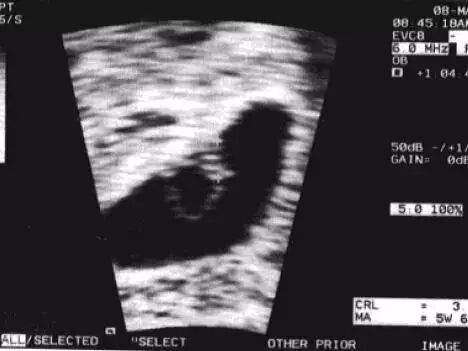

箭头所指为妊娠囊,呈「双环征」,内层为强回声环,外层为低回声环

也可按照公式大致估算:妊娠龄(天 )= 妊娠囊平均内径(mm)+30,但是因妊娠囊形态不规则,且受膀胱充盈程度的影响,故测量值变异较大,仅适用于未见胚芽前的大体估算。

一旦超声观察到了胚芽,就可以测量头臀长(CRL),CRL是估计孕龄的最佳方法之一,但是该指标仅适用于早孕期,在中期妊娠中双顶径(BPD)和头围(HC)被认为与孕龄密切相关。一般情况下可以按照「孕周=胚胎头臀长(cm)+6.5」来估算孕周。

妊娠6周,胚芽贴附在卵黄囊上